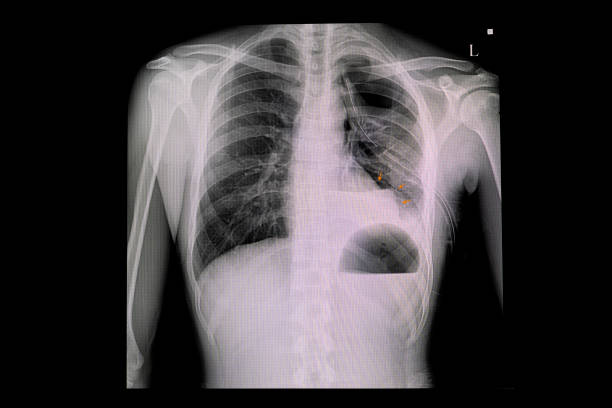

흉부 X선 검사

기흉이 의심되는 환자에게는 흉부 X선 검사를 실시하여 기흉이 있는지 확인할 수 있습니다. 이 방법은 비교적 쉽고 빠르게 기흉을 진단할 수 있습니다.